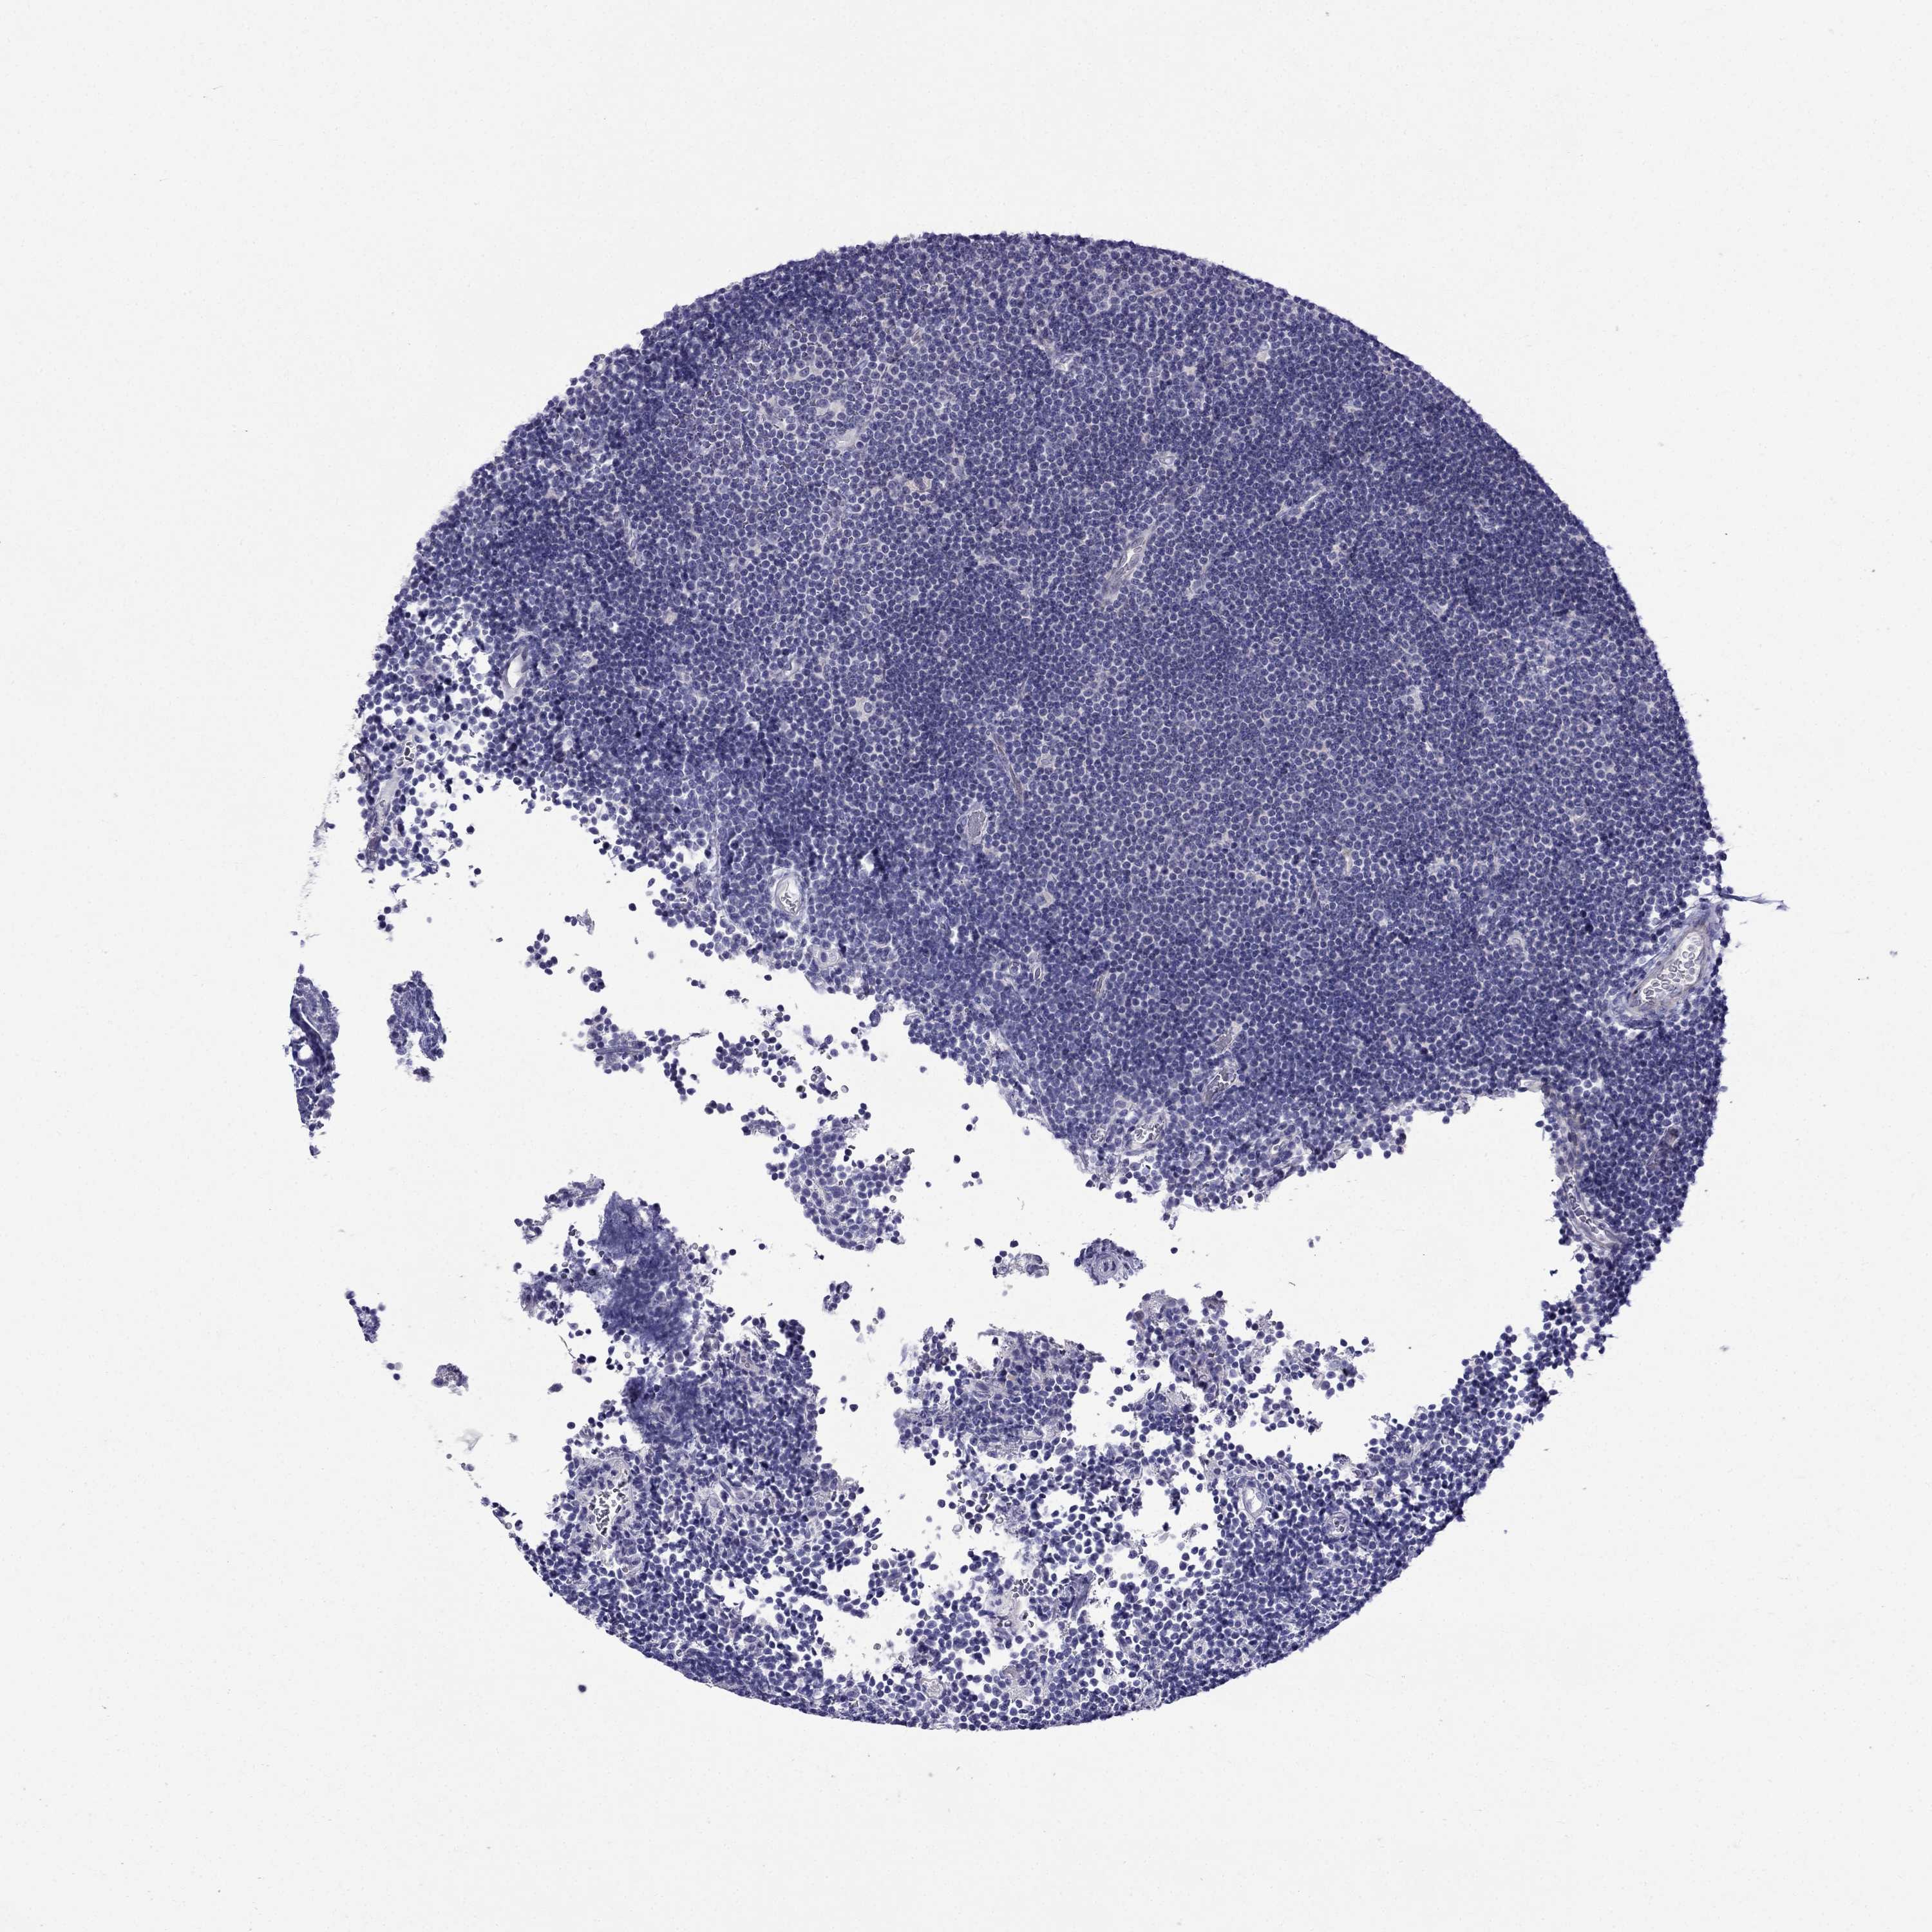

LYMPHOMA - Protein expressioni

A mouse-over function shows sample information and annotation data. Click on an image to view it in a full screen mode. Samples can be filtered based on level of antibody staining by selecting one or several of the following categories: high, medium, low and not detected. The assay and annotation is described here.

Each image is clickable and will lead to virtual microscopy that enables deeper exploration of all samples and also displays staining intensity scores, fraction scores and subcellular localization as well as patient and tissue information for each sample.

Antibody HPA076587

Staining

High

Medium

Low

Not detected

Intensity

Strong

Moderate

Weak

Negative

Quantity

>75%

75%-25%

<25%

None

Location

Nuclear

Cytoplasmic/membranous

Cytoplasmic/membranous,nuclear

Malignant lymphoma, non-Hodgkin's type, Low grade

Malignant lymphoma, non-Hodgkin's type, High grade

Hodgkin's disease, NOS